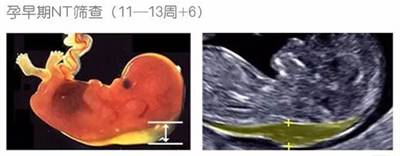

NT即胎儿颈项透明层,是胎儿淋巴系统发育健全之前,少量淋巴液聚集在颈部形成的一处透明层。NT检查就是通过B超检查这一透明层的厚度。在孕早期可联合母体血清标记物,如β-HCG、PAPP-A等估算胎儿染色体异常(主要是21-三体、18-三体)的风险,即所谓的“早期唐氏综合征筛查”(早唐)。“早唐”预测21-三体综合征风险的敏感性约85%~90%(数据来源于英国胎儿医学基金会FMF)。

(图:NT筛查示意图)

NT测量应在11-13+6周,胎儿头臂长(CRL)为45~84mm时进行,取得胎儿的正中矢状切面图,并在胎儿自然伸展姿势时测量。